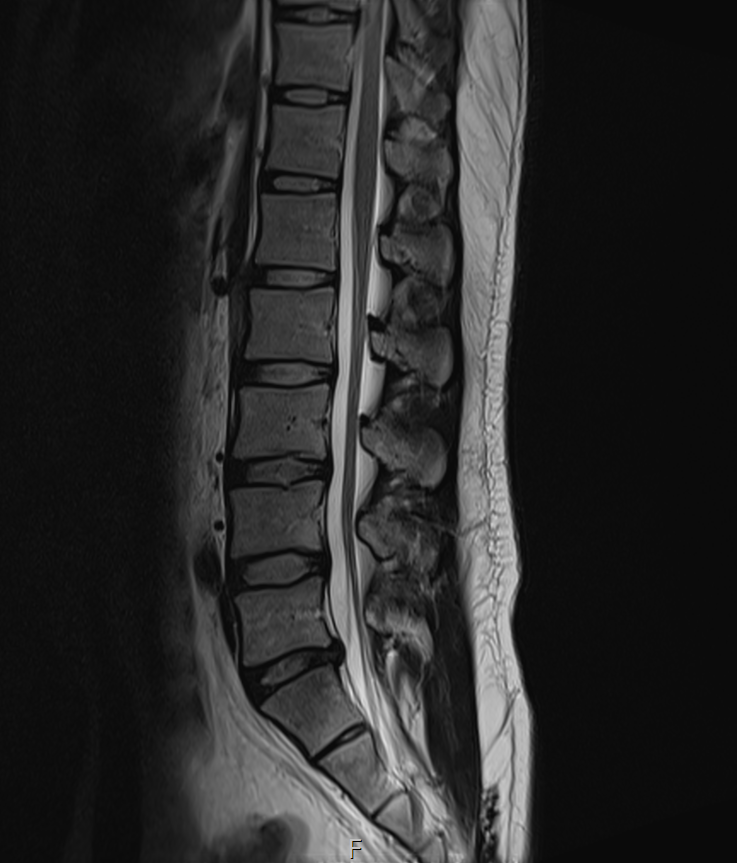

MRI 판독지 및 사진 해석 부탁드립니다.

1년전에 허리가 안좋아서 MRI를 찍었는데 저번주에 경미한 교통사고가 났습니다.

그 후 다리에 저림증상이 있기 시작했고 피가 안통하는 느낌이 들기 시작했습니다.

경미한 교통사고가 다리저림에 원인일 수 있을까요? MRI판독 부탁드립니다 ㅠㅠ

1년전

• 1번 째 사진

1년 전 사진에 비해 허리디스크 상황이 악화된 것으로 생각됩니다. 다리저림은 이로 인한 증상으로 생각됩니다.

그러나, 말씀하신 내용과 검사결과만으로는 교통사고와의 연관성에 대해 단정지어 말하기는 어렵습니다. 증상이 점차 악화되어 발생한 것인지, 교통사고에 의해 갑자기 악화된 것인지에 대한 판단이 추가로 필요하겠습니다.